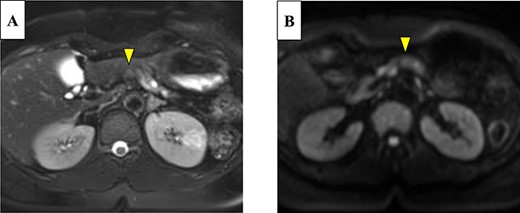

Abdominal-enhanced computed tomography (CT) revealed a low-density pancreatic body tumor of 25 mm in diameter, which was close to the gastroduodenal artery (GDA), and was accompanied by atrophy of the distal pancreatic parenchyma and dilation of the upstream MPD (Fig. 1A). Moreover, CT imaging of the portal phase revealed a filling defect within the splenic vein where it was in contact with the tumor (Fig. 1B). On magnetic resonance imaging, the tumor appeared as an area of signal hyperintensity on T2-weighted and diffusion-weighted images (Fig. 2A and B). On positron emission tomography-CT scan, the tumor exhibited greater uptake of 18F-fluorodeoxyglucose (Fig. 3). Although a definitive preoperative diagnosis could not be made, we suspected pancreatic ductal adenocarcinoma, and distal pancreatectomy with lymph node dissection was scheduled, without neoadjuvant chemotherapy, after obtaining consent from the patient. The pancreas was divided along the left edge of the GDA after mobilization of the artery; however, pathological examination of a frozen section of the pancreas stump was positive for PNET, and therefore a total pancreatectomy was performed (Fig. 4). The duration of surgery was 610 min, the intraoperative blood loss was 195 mL, and blood transfusion was not performed.

(A) Enhanced computed tomography (CT) showed a 25-mm nonhypervascular enhancing mass in the pancreatic body, which was accompanied by atrophy of the distal pancreatic parenchyma, and the upstream main pancreatic duct (MPD) was dilated to 11 mm in diameter (yellow arrow). (B) The mass also invaded the splenic vein (yellow arrow).